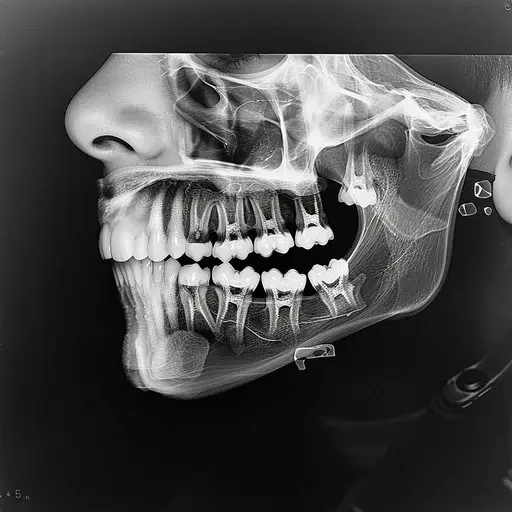

В стоматологии «Доктор Когина» мы придерживаемся принципа индивидуального подхода. Решение о судьбе «восьмерки» принимается после тщательного осмотра и рентген-диагностики.

Когда мы рекомендуем лечение:

• Зуб имеет антагониста (пару на противоположной челюсти) и участвует в жевании.

• Зуб мудрости необходим в качестве опоры для будущего протезирования.

• Зуб занимает правильное положение в дуге и не травмирует слизистую щеки.

• Разрушение коронковой части составляет менее 50%.

Когда удаление неизбежно:

• Сильное разрушение ниже уровня десны: в таком случае качественная реставрация невозможна.

• Неправильный рост: если зуб давит на соседние зубы, вызывая их скученность или разрушение корней «семерки».

• Хронические воспалительные процессы: кисты, гранулемы или постоянные рецидивы перикоронарита.

• Непроходимость каналов: если требуется эндодонтическое лечение, но из-за анатомии корней провести его качественно нельзя.